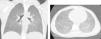

A 5-year-old girl was referred to our tertiary hospital for “recurrent asthma attack” with hypoxemia requiring three hospitalizations in one month. She had no prior history of asthma or atopy, either personally or in her family. She had experienced dyspnea and a dry cough for two months, accompanied by fever for one day at symptom onset and anorexia. On admission, she had tachypnea (57/min) with saturation at 88% in room air, needing supplemental oxygen. Chest auscultation was normal. Chest X-ray showed fine reticulation and diffuse opacities. A detailed environmental history revealed prolonged exposure to domestic turtledove (6 months), with excreta all over the apartment. Her respiratory signs were improved during hospitalization with steroid treatment but worsened upon each discharged at home. CT scan showed diffuse centro-lobular ground glass opacities (Fig. 1). Broncho-alveolar lavage (BAL) confirmed lymphocytic alveolitis with 1500cells/mm3 including 30% lymphocytes (normal range: <10%). The CD4/CD8 ratio was reversed (0.6; normal range: 0.9–2.5). Serum precipitin tests were positive for avian serum (IgG pigeon 91mgA/L, IgG chicken 32mgA/L; normal range<30, FEIA method), corroborated by the presence of specific arch (bird fancier's). Other causes of interstitial lung disease were ruled out through BAL studies, immunological assessments, and infectious disease screenings.